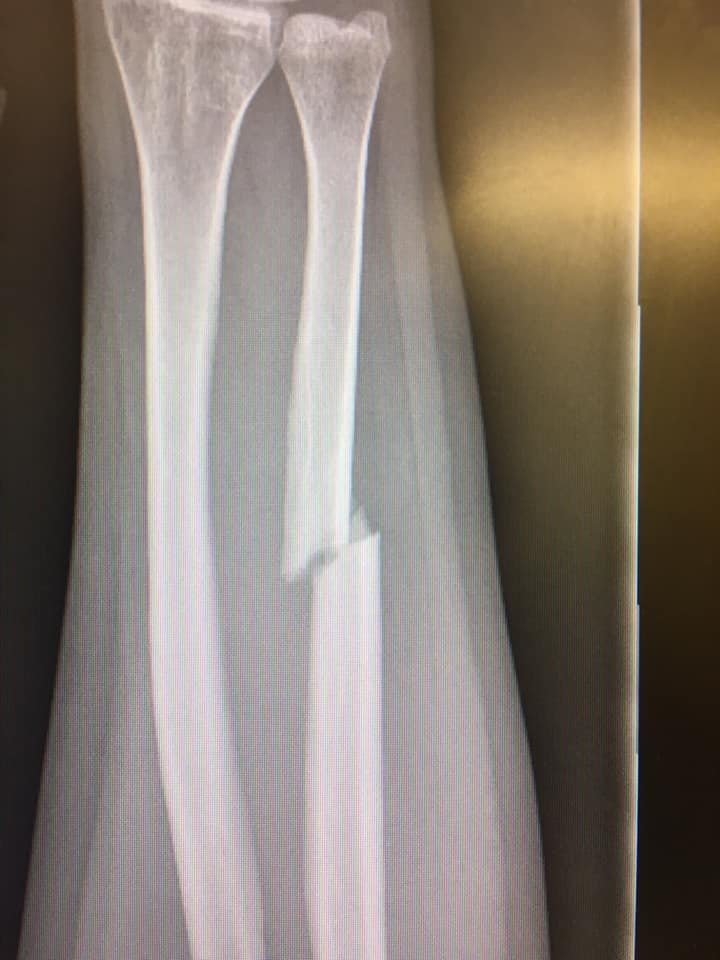

I tried to hold on, but just couldn’t and fell to the left. As you can see, I was not prepared and instinctively put my arm out to try and stop myself, however at that speed and with my body weight behind the impact the small bones in the forearm stood no chance of absorbing that kind of shock!

This is my X-ray from a little while after this incident.